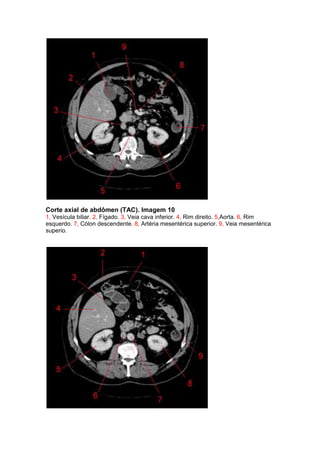

Corte axial de abdômen (TAC). Imagem 10

1, Vesícula biliar. 2, Fígado. 3, Veia cava inferior. 4, Rim direito. 5,Aorta. 6, Rim

esquerdo. 7, Cólon descendente. 8, Artéria mesentérica superior. 9, Veia mesentérica

superio.

Corte axial deabdômen (TAC). Imagem 10 1, Vesícula biliar. 2, Fígado. 3, Veia cava inferior. 4, Rim direito. 5,Aorta. 6, Rim esquerdo. 7, Cólon descendente. 8, Artéria mesentérica superior. 9, Veia mesentérica superio.